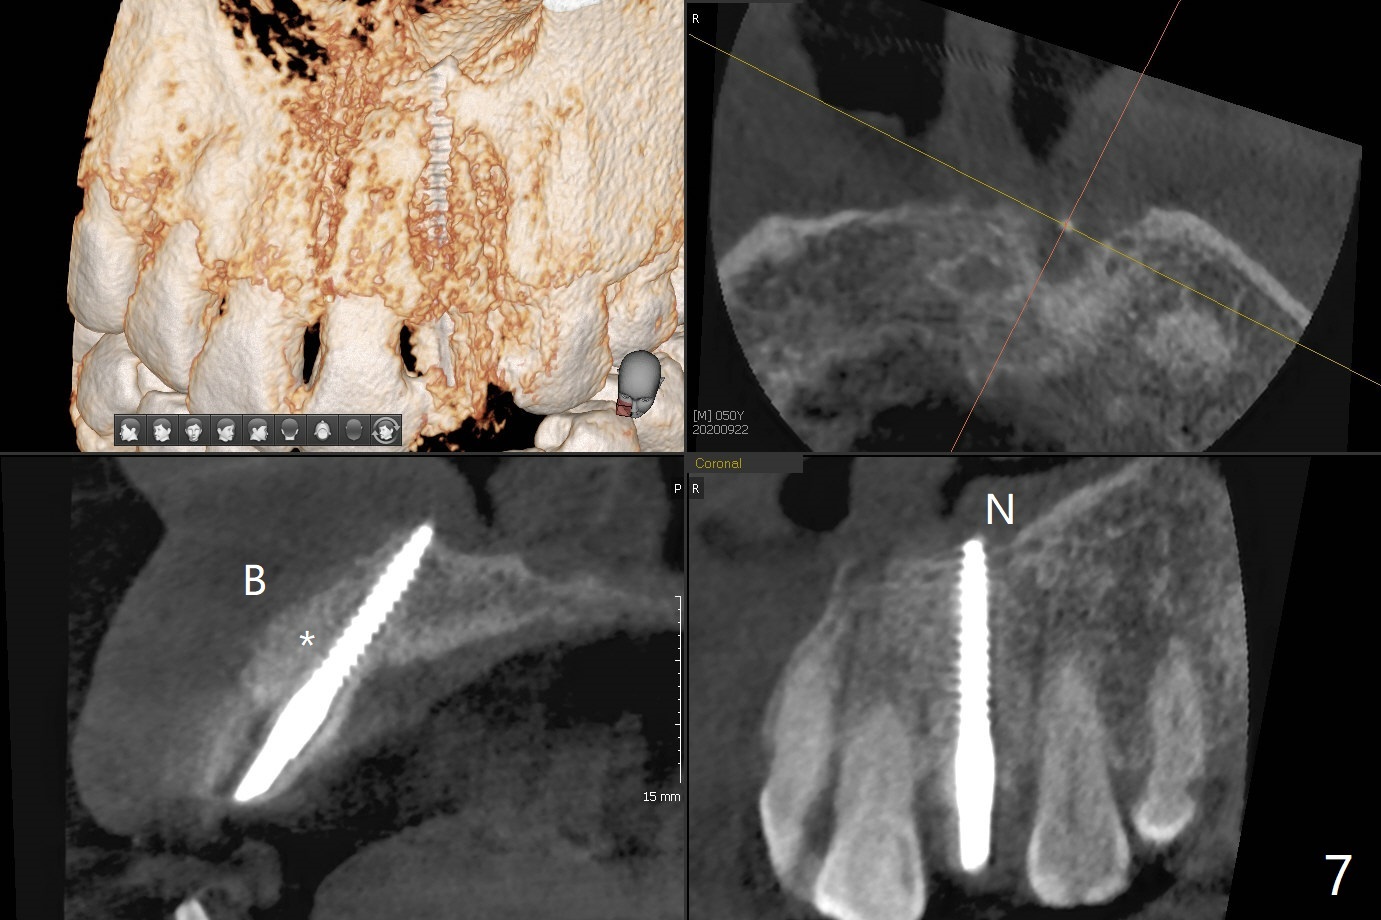

病人回来带来瘘道(图一),不过不会增加难度,病牙去除,它便自动消失。尽管颊侧骨壁完全失去,颊侧牙龈仍丰满(图二),为什么呢?第一,因为粗大牙根存在,第二两旁牙齿,牙槽骨撑着帐篷(侧切牙颊侧牙龈),第三,牙冠。为了防止术后牙龈塌陷,尽量不切开,即刻放置植体(牙根);由于前牙缘故,这次植体不能很大,所以植骨必须过度(over grafting),最后即刻制作临时牙冠,撑住牙龈。这就是所谓每个人进入角色。这个牙根有一种先天性畸形:dens in dent (图三(腭侧观):箭头)。尽管腭侧牙根畸形,腭侧骨壁吸收临床上并不严重,所以钻洞仍偏腭侧。当预定最后钻头还在钻洞时,填入大量粘性骨块(图四:*),细长植体还没有完全卡入鼻底(图五),最后好像可以(图六,七)。植体,骨粉入位(图八),最后临时牙冠出场(图九)。尽管植体小,术后一周临时牙冠仍然可以维持牙龈原有形状(emergency profile,图十:箭头(*:树脂强化牙冠固定))。图十一以不同角度显示瘘道缩小。术后三周取出有些松动的临时牙冠,骨粉虽然还没有被肉芽组织整合,但是显得正常,周围牙龈健康(图十二)。术后4个月牙龈形态正常(图十三),没有触痛;颊侧骨板轻度凹陷(图十四);骨粉仍在原位(图十五)。术后7个月骨粉仍在原位(图十五,十六,但是冠部密度减低(可能骨粉流失,需要牙周或者树脂敷料保护)),没有螺纹暴露。但是牙冠边缘暴露,说明牙龈收缩(图十七,与图十三对比),颊侧骨板仍塌陷(图十八)。插入龈线取得多个目的:修整基台边缘,取模,颊侧牙龈推向颊侧,有利于即将衬里牙冠龈缘进入龈下(图十九)。取模后牙冠边缘(图二十:<)衬里,然后修整,变窄,以便插入龈下,促进颊侧牙龈下降(图二十一,二十二)。术后8个月牙冠粘固前牙龈健康(图二十七,八),牙冠(图二十九)固位后,病人满意(图三十),咬合调整(图三十一),注意腭侧粘固粉流出通道(<)。